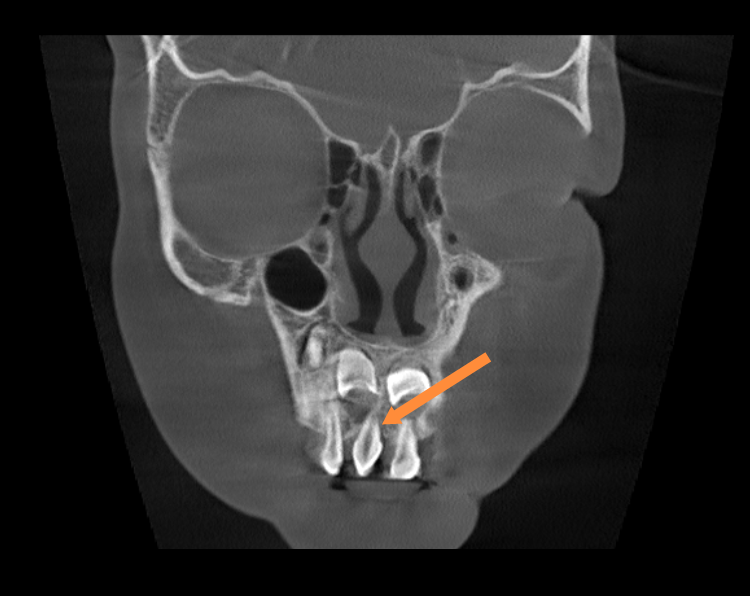

近日,我院口腔科与麻醉科的共同协作下顺利完成首例儿童镇静下口腔治疗。5岁女童因多生牙曾多次到我院口腔科寻求治疗仍无法取得患儿配合。随后在口腔科程敬雨主任与麻醉科唐国值主任的沟通下,最终确定治疗方案:在门诊行镇静监护下进行口腔治疗,家长表示理解并完全赞同实施该方案。

术前口腔CBCT检查